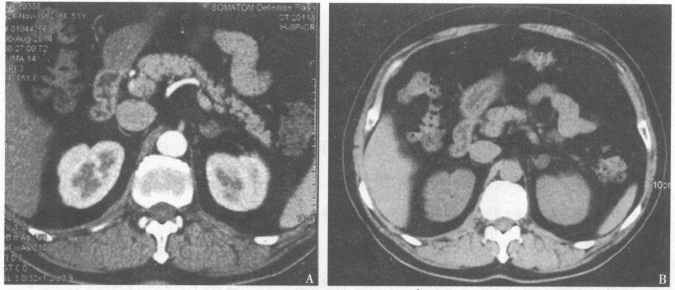

患者男性,40岁,因高血压15年,双下肢无力且反复间断跌倒4年,低血钾3年就诊。患者15年前开始出现高血压,血压最高190/120mmHg(1mmHg=0.133kPa),服用多种降压药物,效果不佳,一般控制在150~160/90~110mmHg左右。4年前突发双下肢无力、跌倒且反复出现。3年前再次发作,血电解质检测发现血钾低,最低为9mmol/L,予以补钾治疗后好转,但低血钾反复出现,难以纠正。多次行腹部及肾上腺超声检查提示双肾、肾上腺等均未见明显异常。该患者既往有多次脑梗死病史2年。查体:体型偏瘦,血压165/110mmHg。为进一步明确诊断,应进行下列哪些检查()【提示】患者完善了腹部CT检查,结果见图3。图3